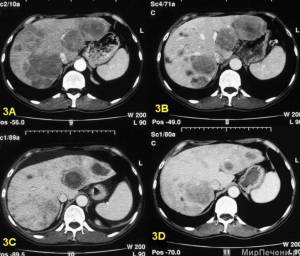

В норме ткань печени гомогенна, имеет большую плотность, чем ткань поджелудочной железы, почек и селезенки. Участи меньшей плотности и округлой форма соответствуют сосудам печени. Воротная вена визуализируется, а печеночная артерия нет.

Патологические образования имеют меньшую плотность, поэтому их легко видеть. Первичная опухоль и метастазы имеют вид круглых образований с меньшей плотностью, чем у паренхимы. Она имеет четкие или размытые границы.

Крупные новообразования деформируют контуры печени. Абсцессы при этом имеют вид гомогенных очагов с четкими границами. Кисты визуализируются как круглые или овальные образования, которые имеют менее плотную структуру, чем абсцессы и опухоли.

Для повышения результативности метода рекомендуется применение контраста. С помощью вспомогательного вещества определяются нормы по форме, величине, структуре, контурам органа, строению долек, состоянию жировой капсулы, внутрипеченочных сосудов и каналов с желчью. Показатели в норме по результатам КТ печеночных тканей визуализируются так:

- структурная однородность паренхиматозной ткани;

- большая плотность тканей, чем у поджелудочной, почек, селезенки, желчного пузыря;

- менее плотные участки в структуре паренхиматозной ткани, соответствующие печеночным сосудам;

- отсутствие визуализации печеночной артерии и протоков с желчью внутри долек;

- выявление воротной вены, общего печеночного и желчевыводящего канала.

Патология определяется по следующим признакам:

- Доброкачественные опухоли (классические кисты, аденомы, гемангиомы) КТ показывает как затемнения с ровными краями с четкими границами, но волнистой структуры. Тип роста — медленный до небольших величин.

- Злокачественные новообразования КТ показывает как затемнения с неровными, нечеткими, бугристыми краями. Тип роста — быстрый, агрессивный до крупных величин.

- Проблемы с протоками для кровоснабжения и оттока желчи визуализируются по изменению насыщенности цвета (чаще — по усилению) в отдельных местах, а также по исчезновению одних канальцев и визуализации других.